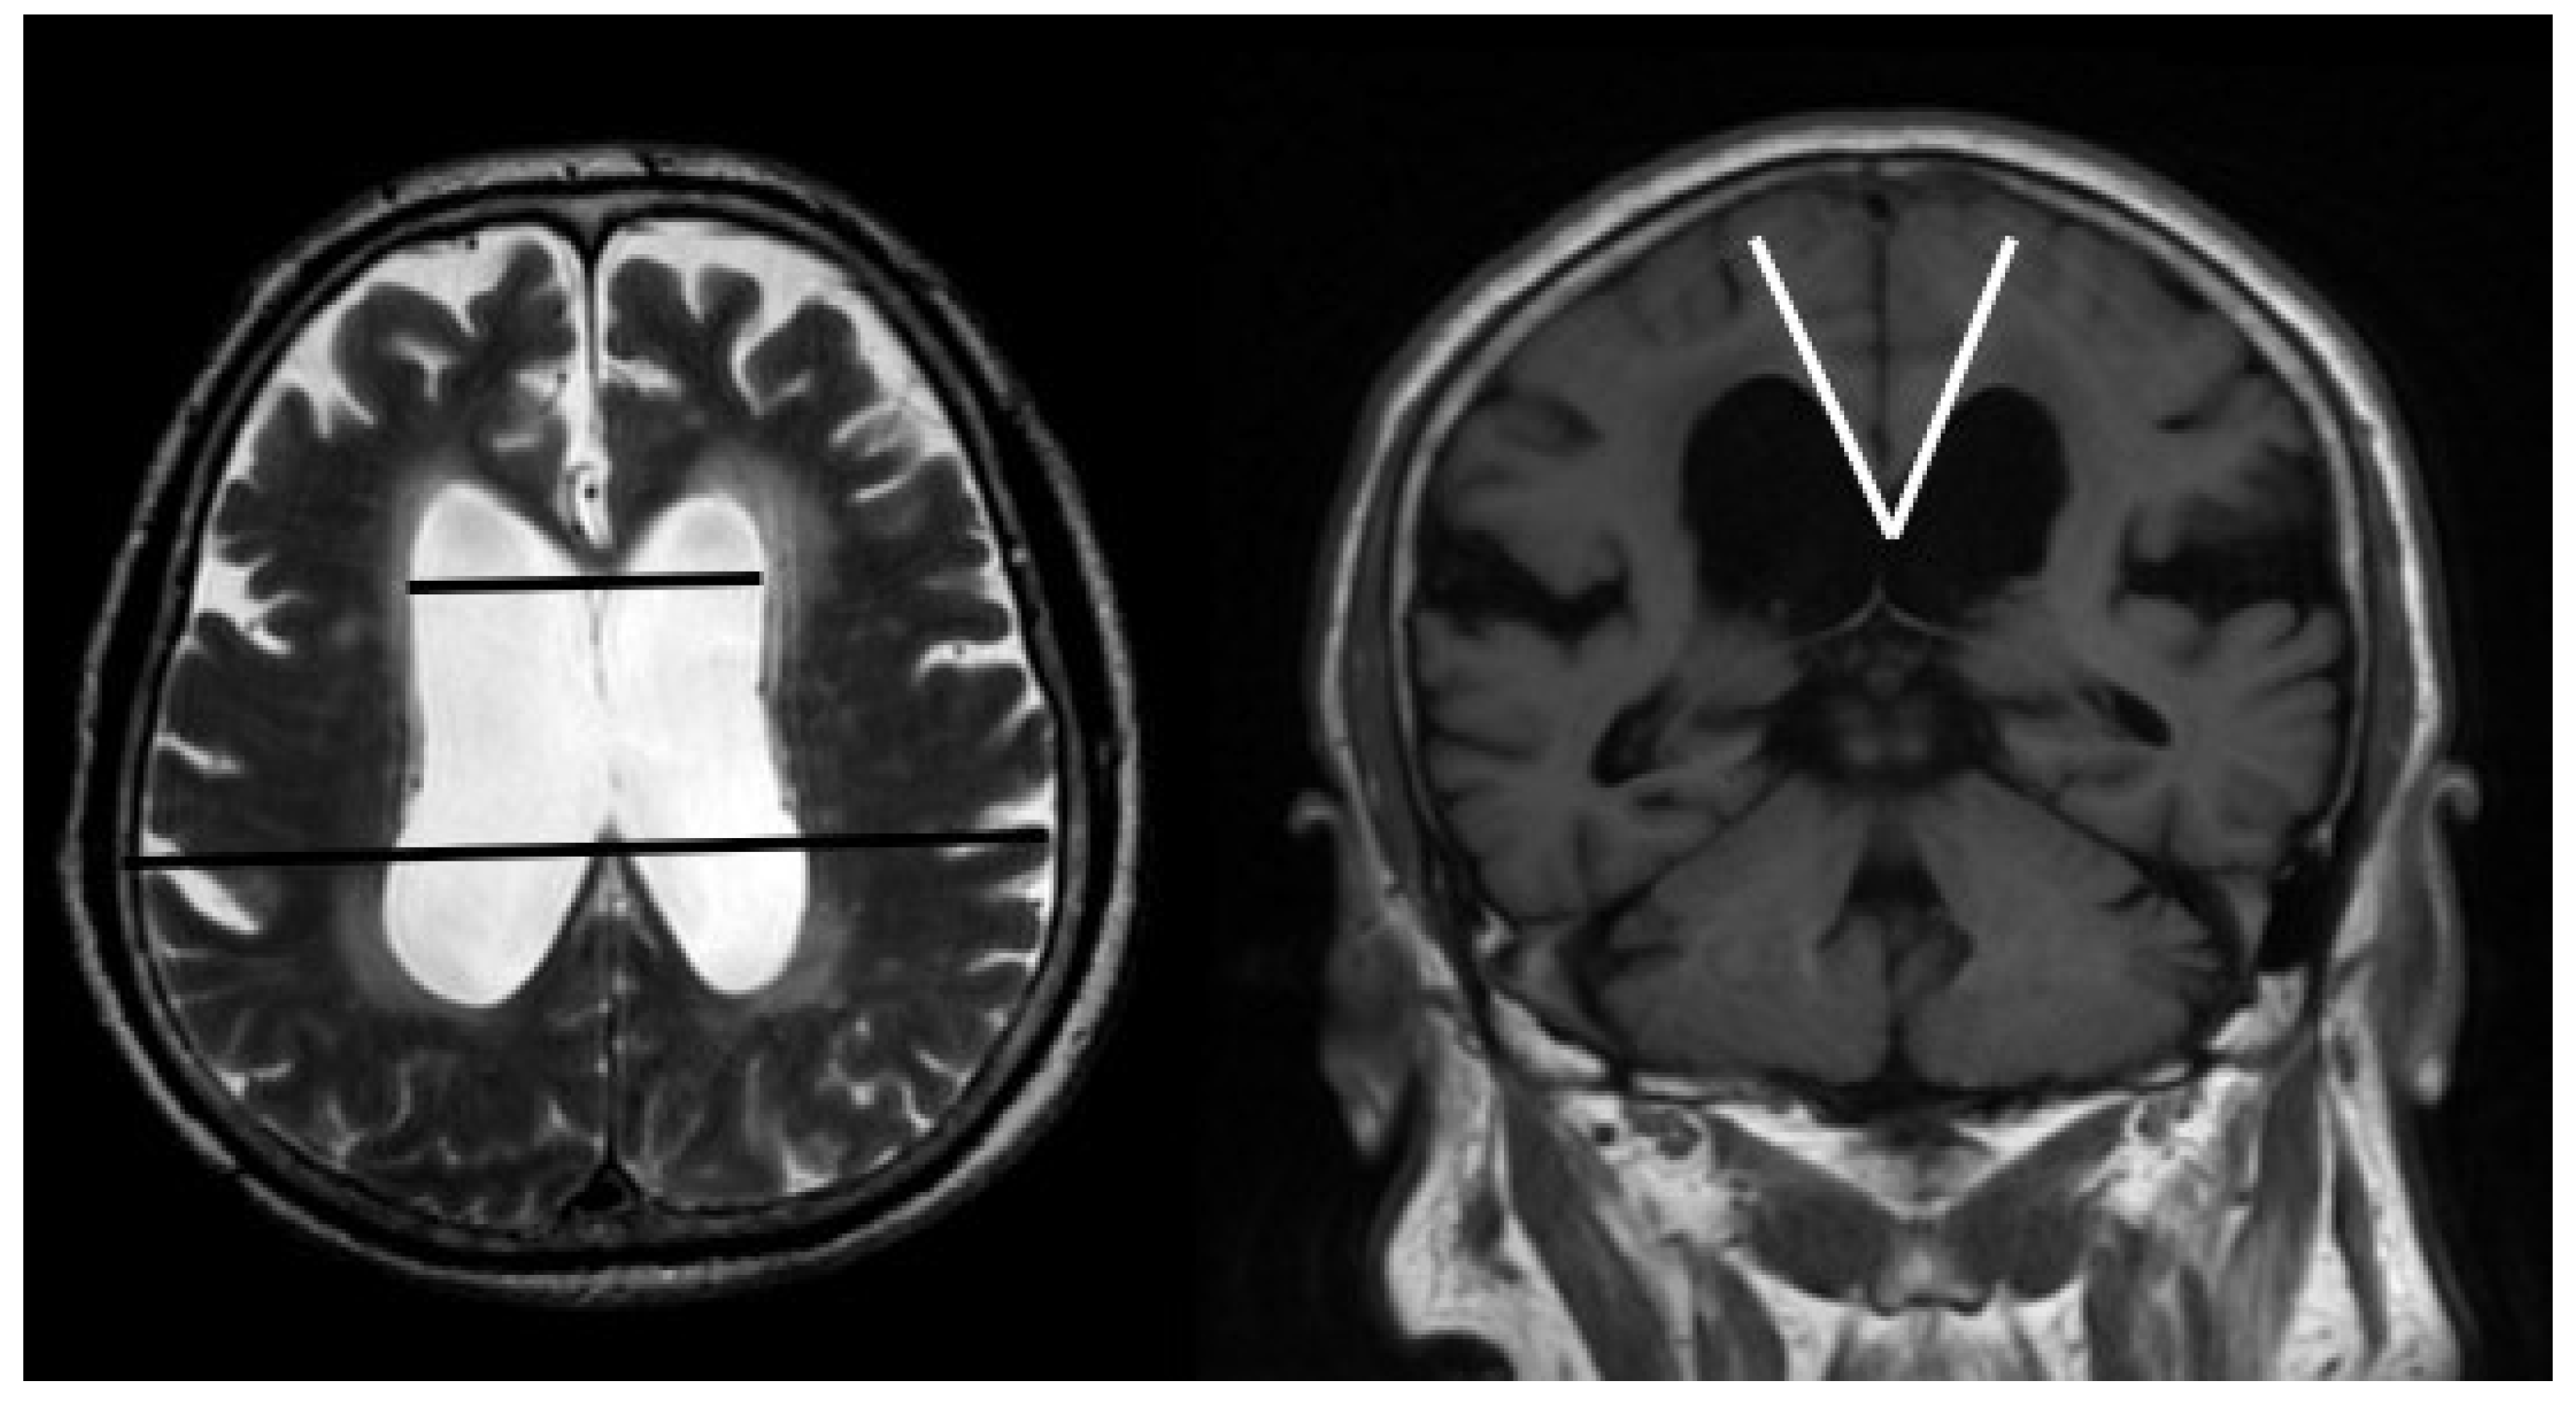

2.2.1. MRI

- Virhammar, J.; Laurell, K.; Cesarini, K.G.; Larsson, E.-M. The callosal angle measured on MRI as a predictor of outcome in idiopathic normal-pressure hydrocephalus. J. Neurosurg. 2014, 120, 178–184. [Google Scholar] [CrossRef] [PubMed]

- Ishii, K.; Kanda, T.; Harada, A.; Miyamoto, N.; Kawaguchi, T.; Shimada, K.; Ohkawa, S.; Uemura, T.; Yoshikawa, T.; Mori, E. Clinical impact of the callosal angle in the diagnosis of idiopathic normal pressure hydrocephalus. Eur. Radiol. 2008, 18, 2678–2683. [Google Scholar] [CrossRef]